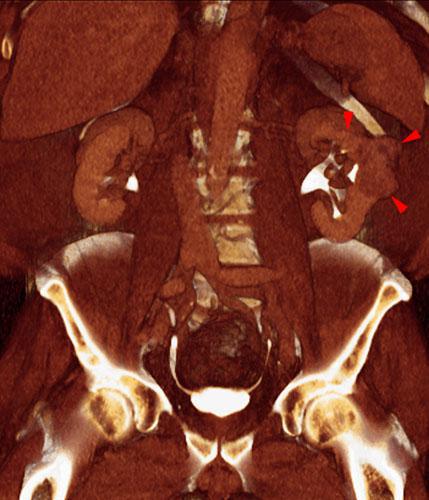

Tumor del seno renal